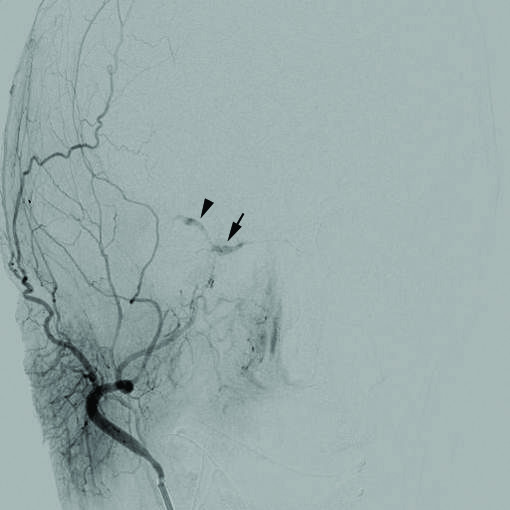

Subarachnoid Hemorrhage

Subarachnoid hemorrhage is hemorrhage that involves the subarachnoid area of the brain.

Causes of subarachnoid hemorrhage include:

- Berry aneurysm rupture (85% of cases)

- Arteriovenous (AV) abnormalities

- Anticoagulation complication